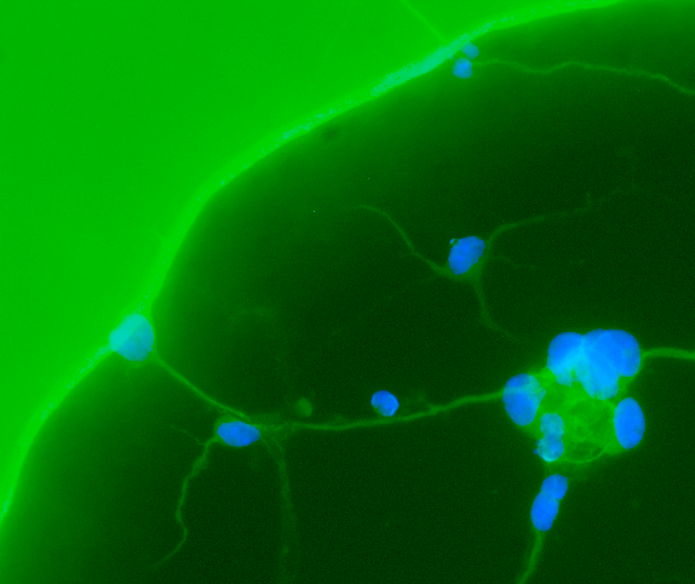

Current pharmacotherapies for major depression disorder and major anxiety disorder have problematic disadvantages, the most important being high resistance in the population. Novel treatments such as the hallucinogens (i.e. LSD, Psilocybin (Psilocin), Ketamine), while robust, possess their own weaknesses such as the potential for abuse and the strain of hallucinogenic side-effects on healthcare infrastructure. In recent years there has been a push to find novel, so-called next-generational psychedelic treatments that retain the positive anti-depression or anxiolytic properties without the hallucinogenic side-effects. My current work in the lab of Dr. Argel Aguilar Valles at Carleton University involves utilizing molecular neurobiology and behavioural neuropharmacology to study the effects of psychedelic compounds on neuroplasticity and depression-like behaviour in murine models.